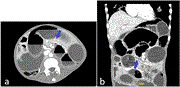

Assessment of revascularization impact on microvascular oxygenation and perfusion using spatial frequency domain imaging

Ikeoluwapo K Bolakale-Rufai and others

Journal of Surgical Case Reports, Volume 2023, Issue 7, July 2023, rjad382, https://doi.org/10.1093/jscr/rjad382